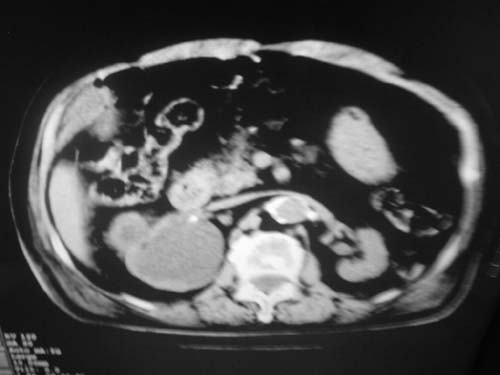

以下是引用余辉在2009-3-11 21:12:00的发言:[br]1肝脾多发钙化结节2右肾结石,右肾积水

以下是引用jiangjing在2009-3-12 17:05:00的发言:[br]1肝脾多发钙化结节2右肾结石,右肾积水 3胆囊炎[br] [br] 左肾囊肿